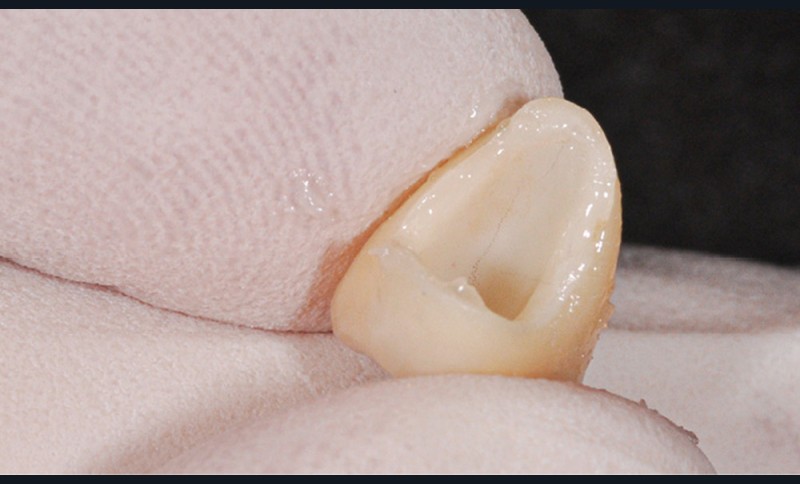

La méthode la plus efficace est probablement le pré-scellement de la suprastructure sur un duplicata du pilier. Ce dernier peut être livré par le laboratoire en même temps que les pièces prothétiques, réalisé alors le plus souvent en résine.

Une autre méthode, réalisable au cabinet, consiste à utiliser du silicone light en pistolet pour remplir l’intrados et, après la prise, désinsérer pour obtenir un duplicata rapide et économique (fig. 3).

Au moment du scellement, la suprastructure est remplie du matériau d’assemblage, puis positionnée entièrement, mais sans pression, sur ce duplicata, et immédiatement retirée pour être positionnée sur le pilier implantaire en bouche (fig. 4).